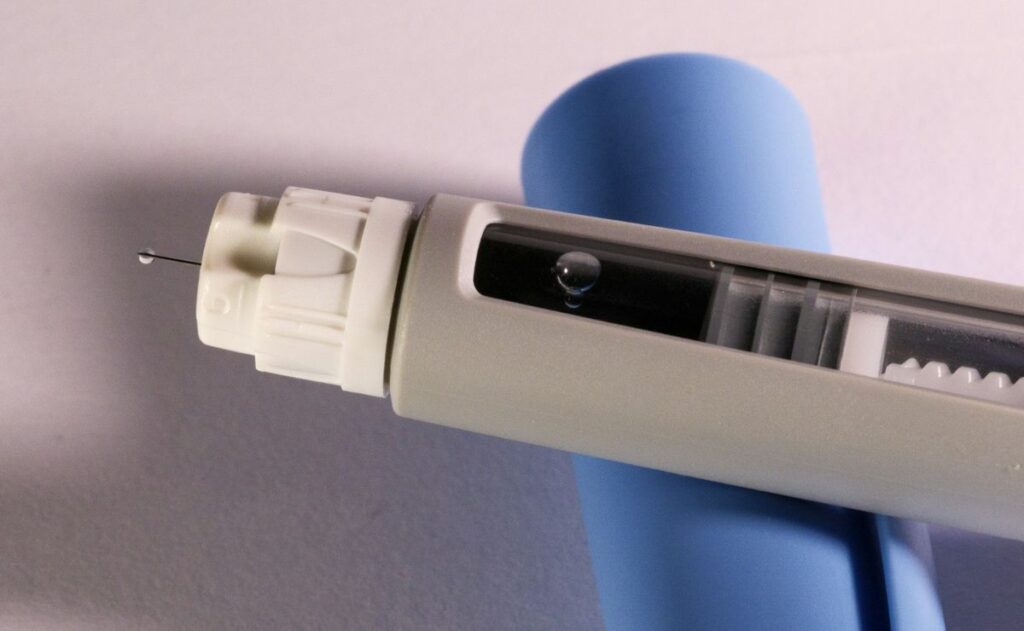

Las autoridades informó que estos productos carecen de registro sanitario para su distribución en territorio nacional, lo que significa que no han sido evaluados en cuanto a su seguridad, calidad y eficacia. Se vendían a través de plataformas de comercio electrónico, sitios web y aplicaciones móviles en presentaciones como gotas, parches, viales y jeringas prellenadas.

Tras análisis técnico-documental, Cofepris descubrió irregularidades graves: algunos productos de la marca Dr. Pen contenían en realidad Semaglutida —otro principio activo— y presentaban crecimiento bacteriano. Además, la pluma de aplicación de esta marca estaba reetiquetada y su registro sanitario se encuentra cancelado.